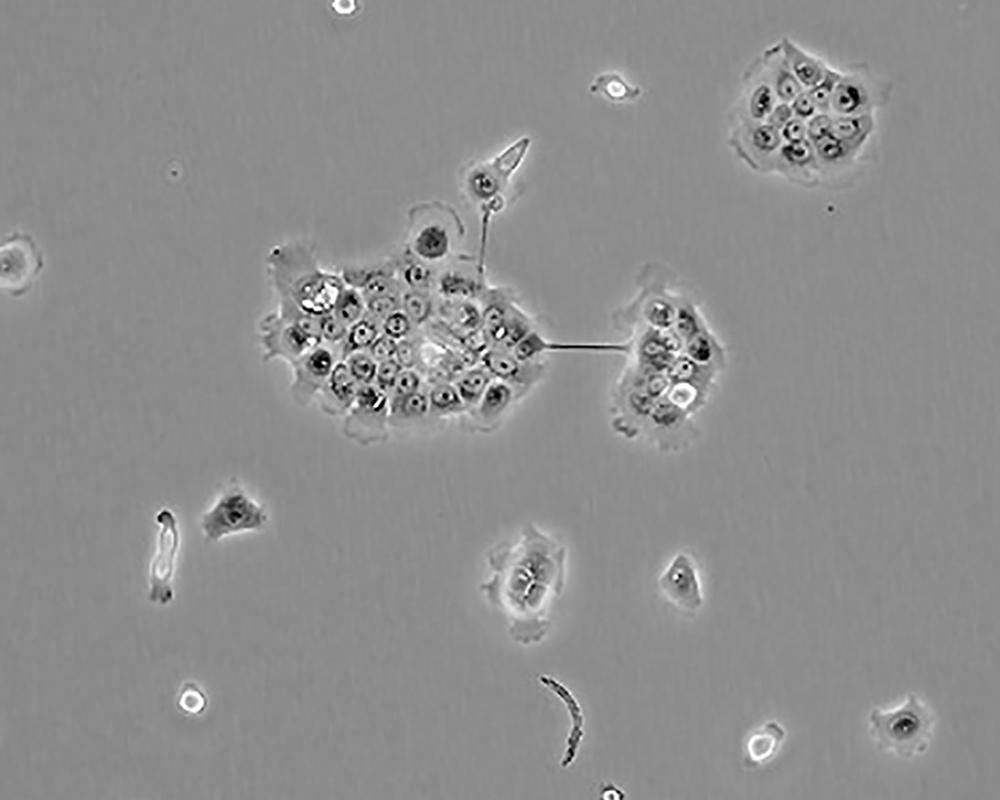

BxPC-3(BxPC3)

產(chǎn)品名稱 BxPC-3(BxPC3)

中文名稱 人原位胰腺腺癌細(xì)胞

組織來源 胰腺導(dǎo)管腺癌;女性

生長特性 adherent

形態(tài)特征 epithelial

細(xì)胞描述 The cells do not express the cystic fibrosis transmembrane conductance regulator(CFTR). A CFTR positive pancreatic line, Capan-1 is available.